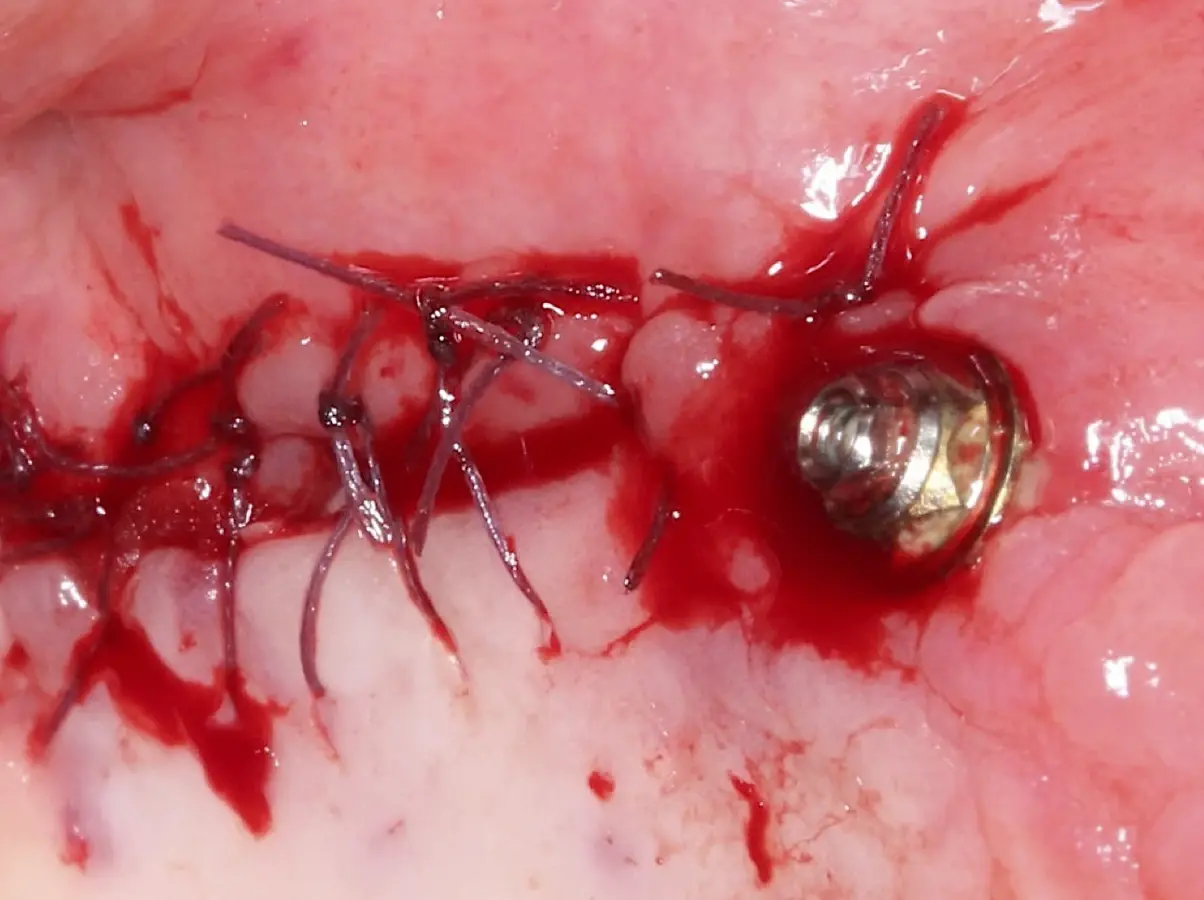

Figura 22. Afrontamiento de colgajo y sutura.

Figura 30. Liberación del colgajo, afrontamiento sin tensión y sutura.